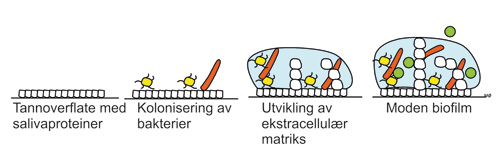

I munnhulen hos alle mennesker lever hundrevis av ulike arter mikroorganismer, både bakterier, virus og sopp (1). Over 700 ulike bakteriearter er til nå identifisert i det orale miljøet og det finnes opp mot en million mikroorganismer per kubikkmillimeter saliva (2). Disse lever i komplekse samfunn med hverandre og er ofte organisert i tynne lag av mikroorganismer - biofilm - festet på overflaten av munnhulens ulike bestanddeler. Ett eksempel er plakk på tannoverflater (3,4). Biofilmen bygges opp på en ren, fuktig flate dekket av salivaproteiner som bakterier kan feste seg til ved hjelp av mikroskopiske utstikkere eller overflatemolekyler i celleveggene (figur 1). Bakteriene fester seg til hverandre og kommuniserer med hverandre med signalmolekyler (3). De skiller også ut proteiner, polysakkarider og andre substanser fra cellen. Dette blandes med substanser fra saliva og danner en ekstracellulær matriks som holder hele samfunnet sammen.

Figur 1. Utvikling av biofilm på rene tannoverflater.